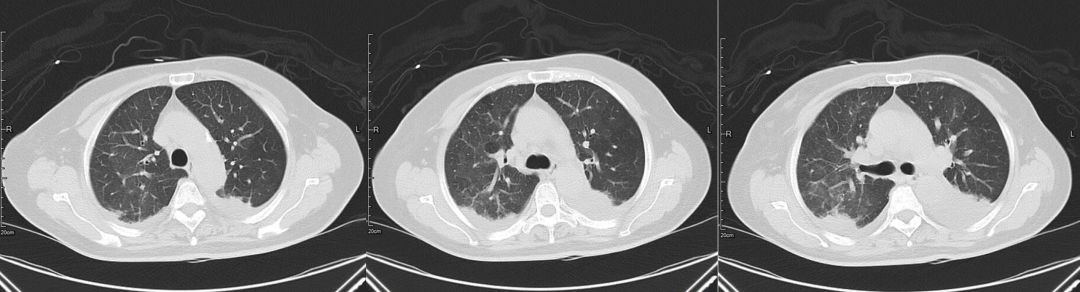

治疗前(2019-03-05)

胸部CT:两肺多发斑片状渗出影,部分实变,两侧胸腔积液,双下肺膨胀不全,两肺门增大,纵隔内多发淋巴结。

3、辅助检查。胸部CT:双肺多发斑片状渗出性,部分实变,双侧胸腔积液。心超:左心增大伴中度二尖瓣关闭不全、主动脉瓣退行性变伴中度关闭不全、肺动脉高压伴轻中度三尖瓣关闭不全、房间隔膨出瘤(未破裂),EF 60% 正常。

该患者老年女性,社区发病,无发热、有轻微呼吸道症状,以胸闷表现为主;查体:肺部有啰音,白细胞、CRP等炎性指标升高;胸部影像学:斑片状磨玻璃影、部分实变、间质性改变,伴或不伴胸腔积液,似乎符合社区获得性肺炎(CAP)诊断标准……

该病例中患者影像学提示双肺多发弥漫性渗出影,没有及时鉴别诊断,笼统诊断为肺部感染性疾病,该影像不是肺部病原菌感染特有的表现,它不是感染的代名词。